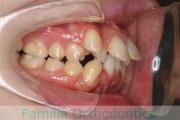

でこぼこと口元が出ている横顔が気になるとのことで来院されました。重度の叢生(ガタガタ)と側方へのズレがあるため、アンカースクリューを併用したマルチブラケット法にて治療を行いました。3年弱、35回程度の通院をしていただきました。叢生が強いため、部分的にガタガタが再発・後戻りするリスクが高いケースでした。

- ≫治療後

-

上顎

下顎

前歯の関係など

右側

正面

左側